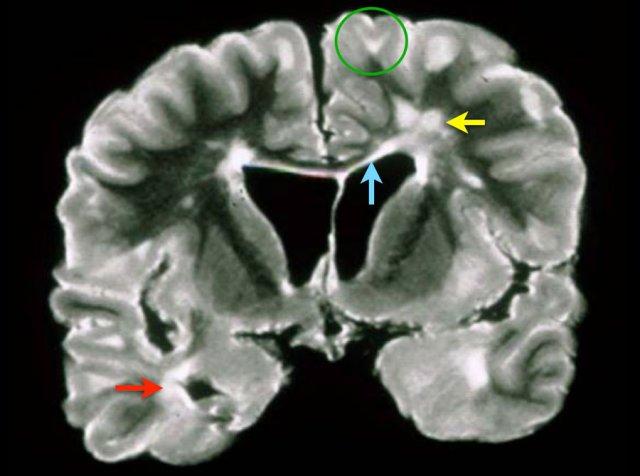

Đây là hình ảnh T2W mặt phẳng coronal của mẫu não có tổn thương đa xơ cứng. Các tổn thương ở chất trắng sâu (mũi tên vàng) không đặc hiệu và có thể gặp trong nhiều bệnh lý khác nhau.

Đặc trưng cho bệnh đa xơ cứng trong trường hợp này bao gồm:

- Tổn thương cạnh vỏ não (vòng tròn xanh lá) – tiếp xúc trực tiếp với vỏ não (không có chất trắng xen kẽ)

- Tổn thương quanh não thất – tiếp xúc trực tiếp với não thất

- Tổn thương thể chai (mũi tên xanh dương)

- Tổn thương thùy thái dương (mũi tên đỏ)